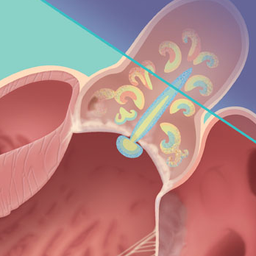

Calcific aortic stenosis involves progressive narrowing and stiffening of the aortic valve, through which blood flows from the heart to the rest of the body. Aortic stenosis affects 1% to 2% of adults older than 65 years and about 12% of those older than 75 years in the US.

Calcific Aortic Stenosis: A Review Podcast (19:15) 0:00 / 0:00 Abstract Importance Calcific aortic stenosis (AS) restricts the aortic valve opening during systole due to calcification and fibrosis of either a congenital bicuspid or a normal trileaflet aortic valve. In the US, AS affects 1% to 2% of adults older than 65 years and approximately 12% of adults older than 75 years.